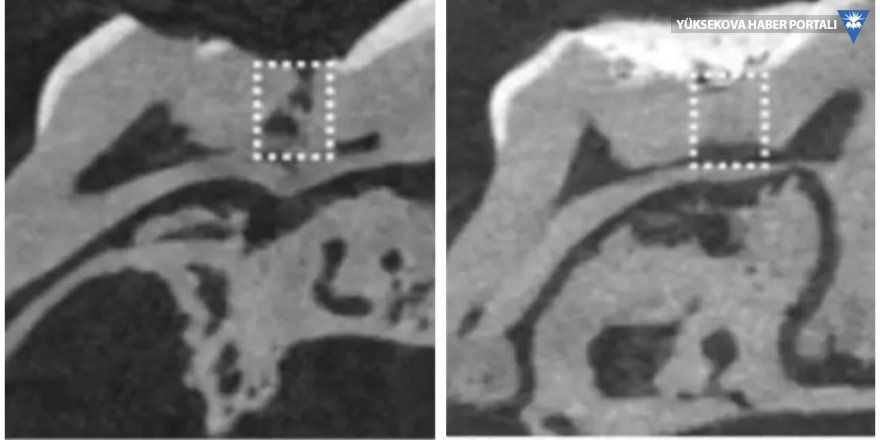

Alzheimer hastalığını tedavi edebilmek için geliştirilmiş olan Tideglusib adındaki yeni bir ilacın fareler üzerinde yapılan denemelerinde, doğal bir diş doldurma mekanizmasını harekete geçirdiği keşfedildi. İlaç, kök hücreleri uyararak, dentin oluşumunu tetikliyor.

Dentin oluşumu diş ömrü boyunca sürdüğünden, yaşlandıkça dentin kalınlığı artıyor. Bu yüzden dentin aynı zamanda insan dişlerine sarı rengini veriyor. Minenin kalınlığı azaldıkça, alttaki dentin tabakası daha fazla görünür hale geliyor. Dişler, aslında herhangi bir dış yardım almadan doğal olarak dentini ancak belli koşullar altında üretebiliyor. Diş özünün (pulpa), enfeksiyona (örneğin çürümeye) veya travmaya maruz kalarak, iç yapının üretimini başlatması gerekiyor. Ancak öyle olduğunda bile, dişin doğal olarak yeniden üretebildiği katman çok ince oluyor; yani genellikle derin olan çürüme kaynaklı oyukları onarmaya yetmiyor. Bilim Fili sitesinden Sevkan Uzel’in haberine göre , Tideglub ilacı bu durumu değiştiriyor, çünkü “dentin” oluşumuna köstek olan GSK-3 enzimini kapatıyor.